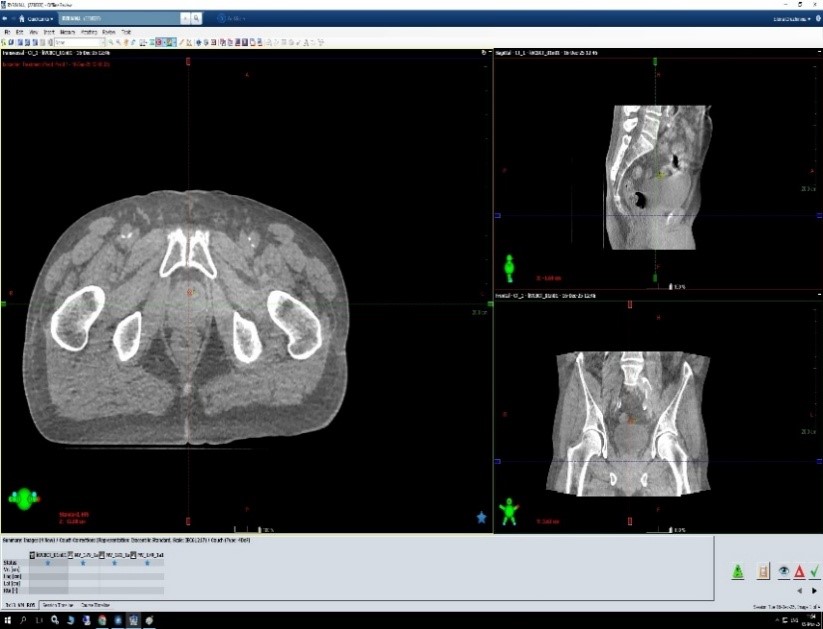

Сравнение МVCBCT и KVCBCT изображений малого таза

Преимуществом kV СВСТ является высокая точность визуализации мягких тканей по сравнению с MV CBCT, что критично для точного облучения опухолей, расположенных в малом тазу пациента. Кроме того kV СВСТ широко применяется при стереотаксической лучевой терапии (SBRT) опухолей, расположенных в грудной клетке.

Главное преимущество CBCT перед планарными снимками — получение высококачественных трехмерных изображений костных структур и мягких тканей выбранной области.